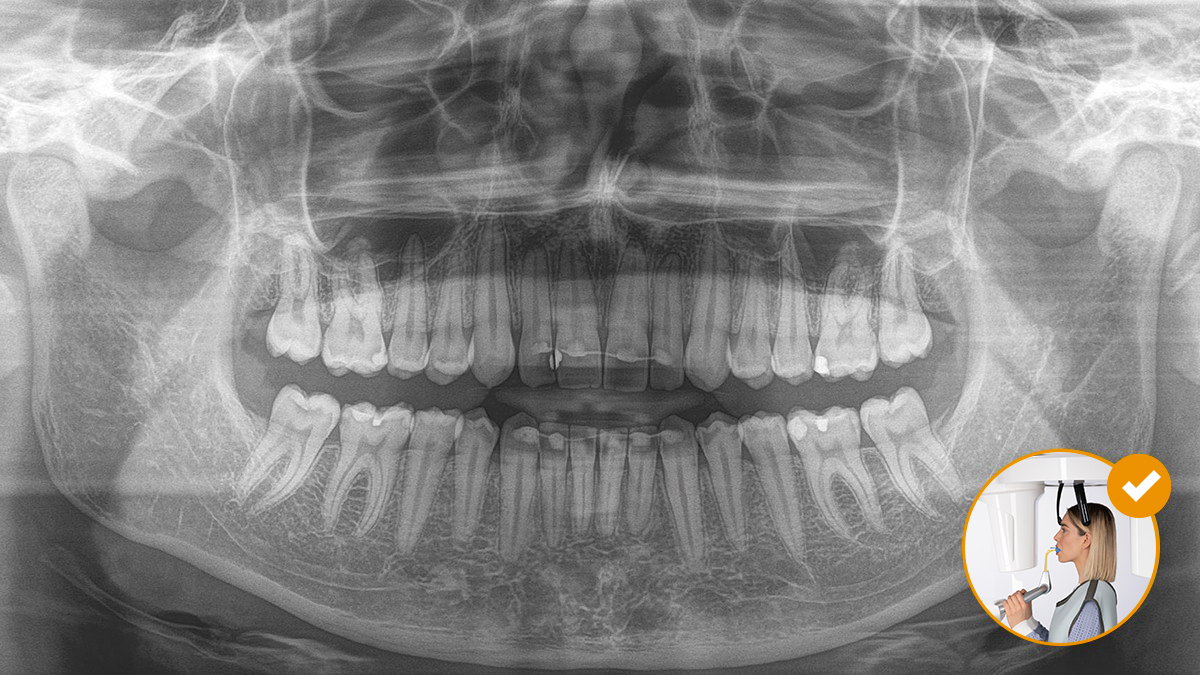

Un positionnement correct du patient mène à une qualité d’image élevée, essentielle pour un diagnostic fiable et améliore l’expérience du patient.

Voici notre concept à 10 points pour un positionnement facile du patient et une imagerie radiographique efficace. Il repose avant tout sur deux principes : une qualité d’image supérieure et le confort du patient et de l’assistant.

Le fonctionnement du bloc de morsure occlusale ne pourrait pas être plus simple. Avec l’aide des symboles et des couleurs affichés sur l’écran de l’appareil à rayons X, les praticiens disposent de toute l’information nécessaire pour un réglage fin optimal de l’appareil. Les flèches lumineuses indiquent la direction dans laquelle l’unité doit être déplacée pour obtenir une inclinaison idéale de la tête. L’appareil s’arrête automatiquement une fois que la position correcte est atteinte.